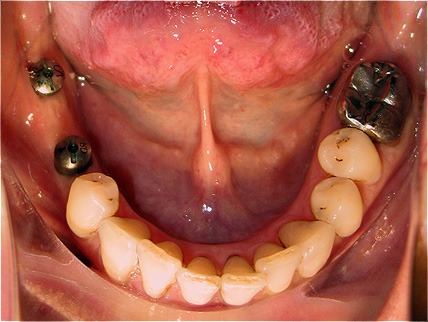

Caso 3 - Desdentado total reabilitado com prótese acrílica removível inferior, barra e clips para retenção e estabilidade

![]() |

![]() ![]() |